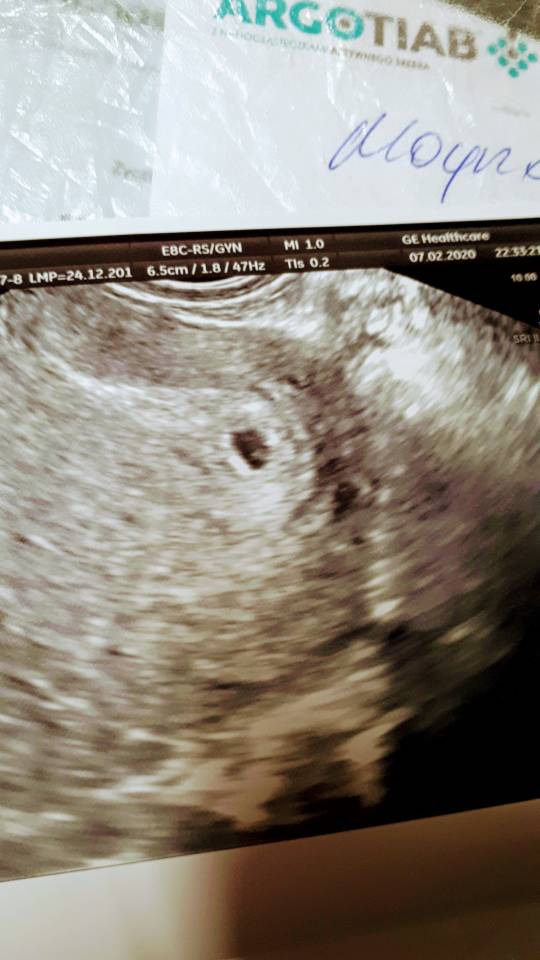

Hej. To bardzo wczesna ciąża. Wg gin wszystko ok. Jestem po cp w styczniu 2019

Oglądam foto i czy tam nie ma 2 pęcherzyków? Czy wyobraźnia szaleje.

Kolejna wizyta 25.02

Już wszystko wiem. 1 jest. Hi tylko taki obraz.